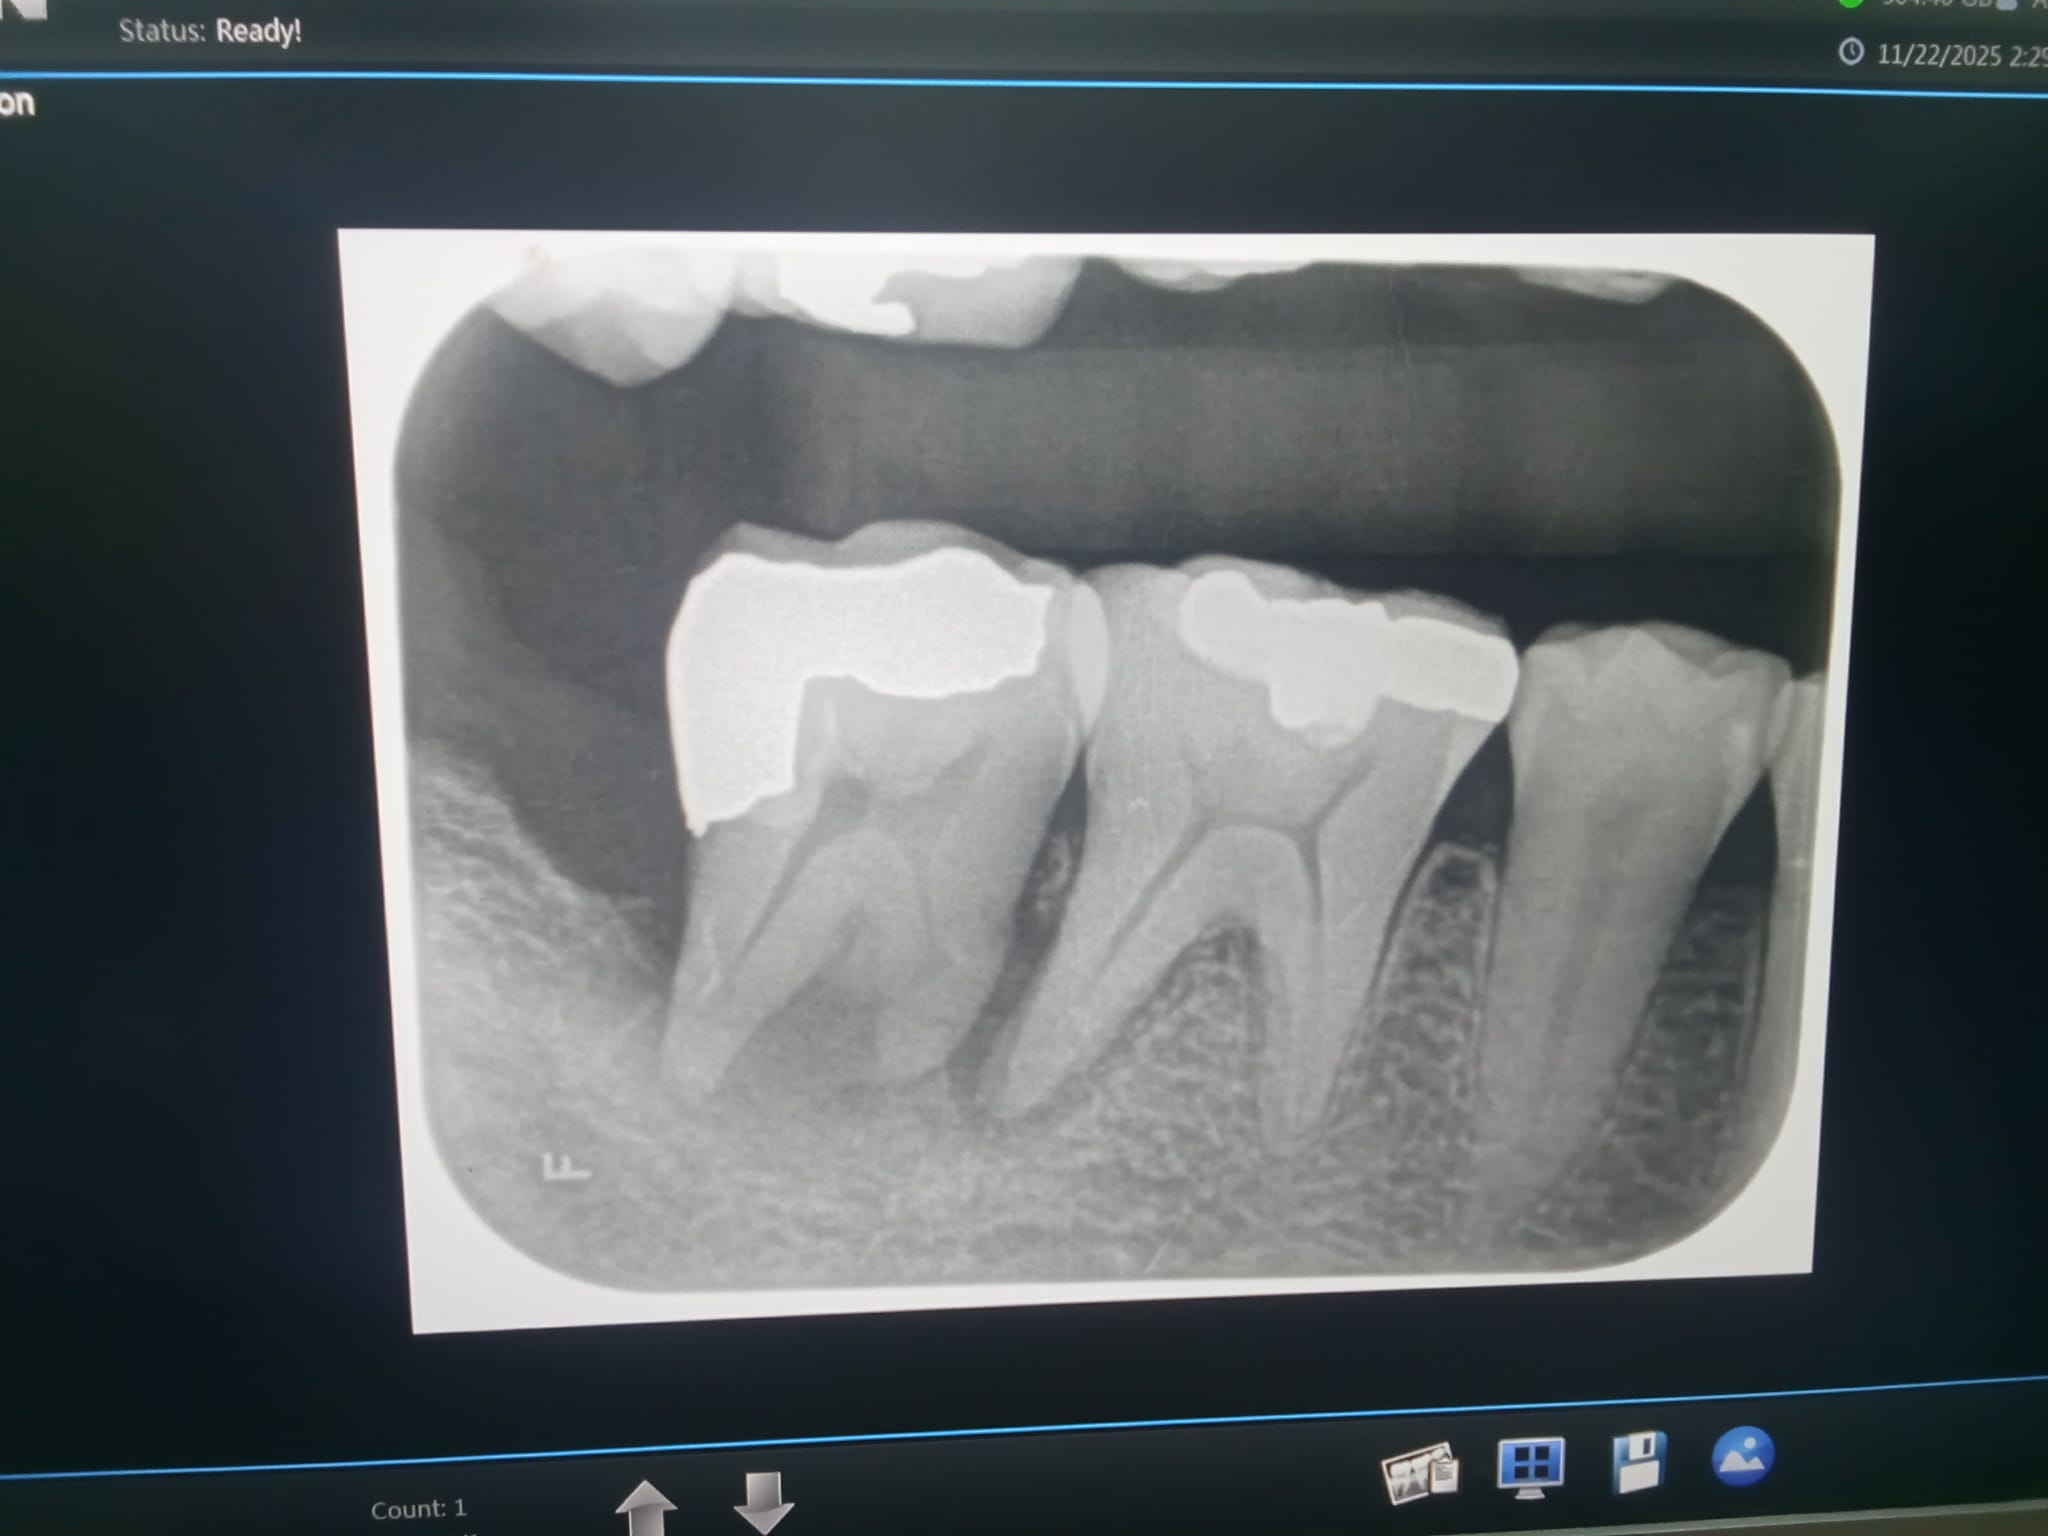

เอ็กซเรย์ออกมาได้แบบนี้

ที่2 ให้ถอน เพราะ เนื้อฟันน้อย รากฟันเหลือนิดเดียว บลาบลาบลา (ให้ดูภาพเอกซเรย์)

ที่ 3 ที่ครอบไว้แตก (ตอนฟังเข้าใจว่าครอบ) ให้แพทย์เฉพาะทาง แก้ให้ ครอบใหม่(ที่นี้ ไม่ได้ให้ดู ภาพ เอกซเรย์)